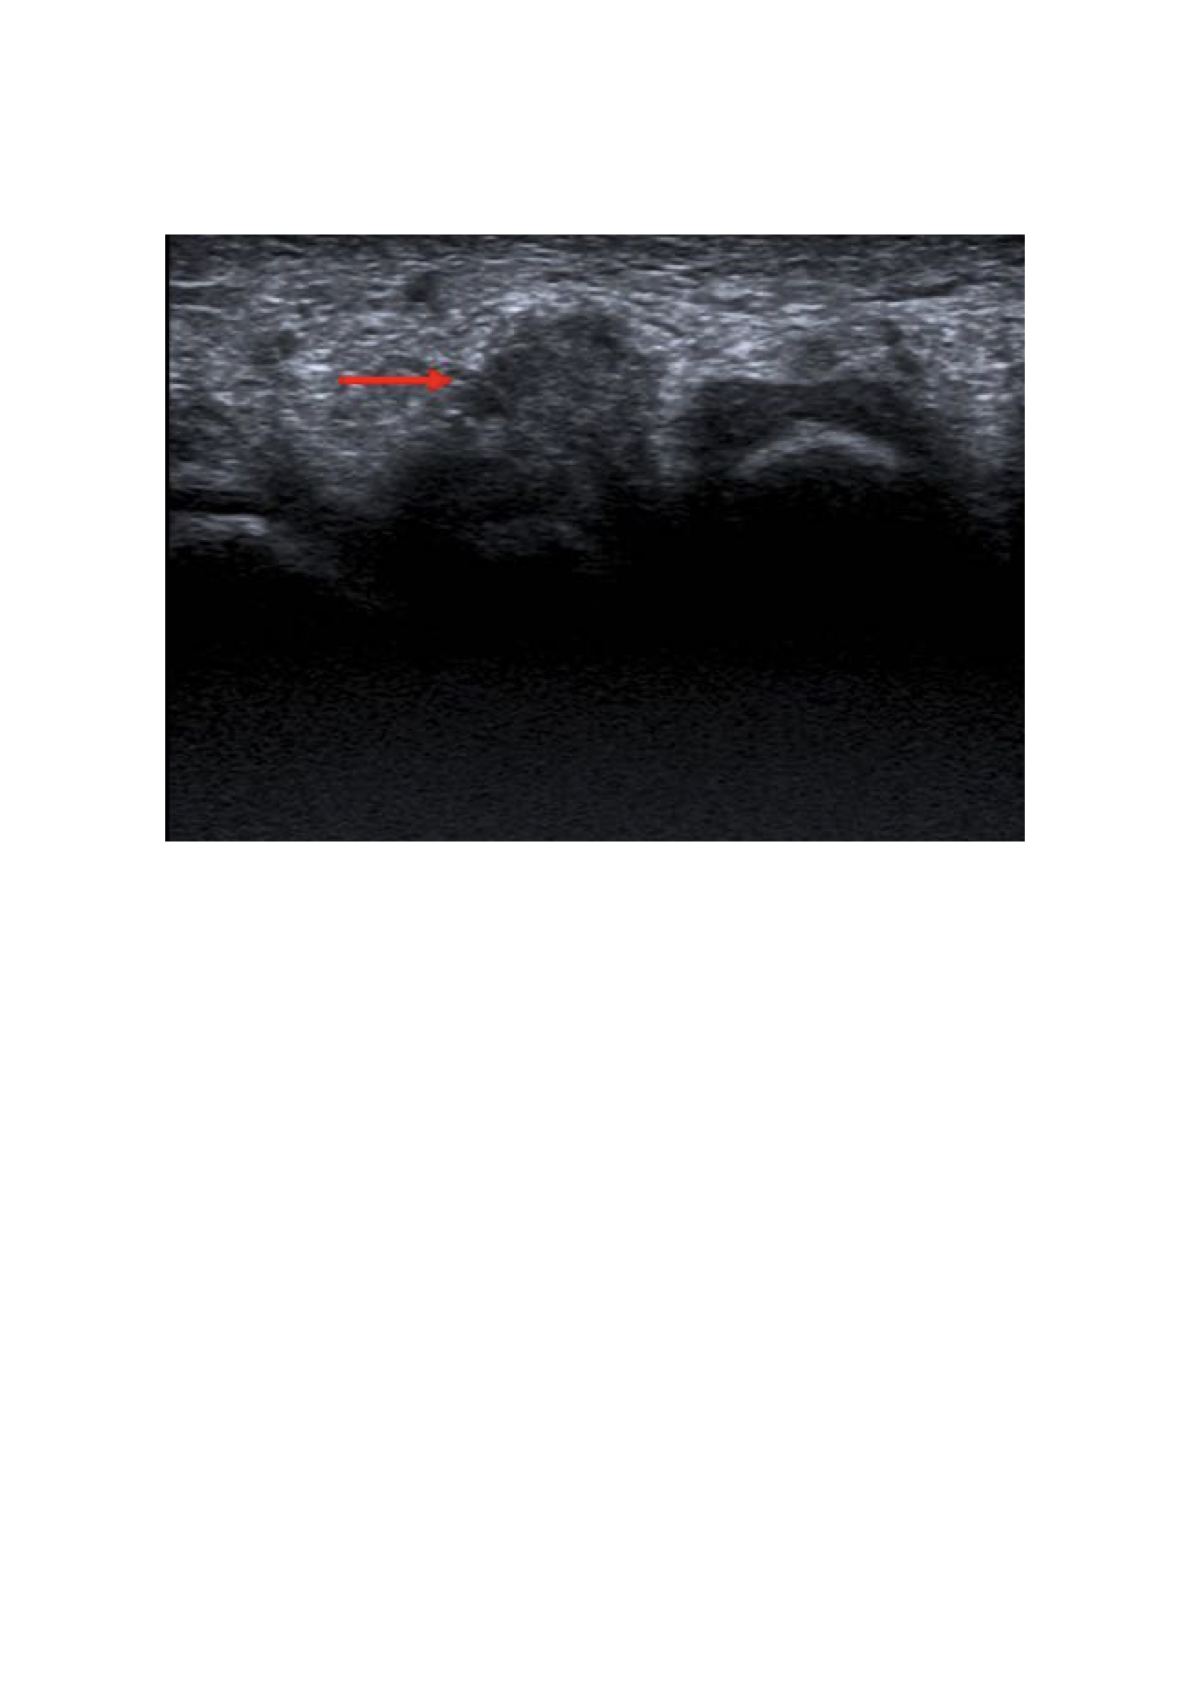

Hallazgos ecográficos

En corte transversal por acceso plantar se identifica una masa hipoecoica redondeada homogénea de bordes bien definidos en tercer espacio interdigital de 7 mm, compatible con neuroma de Morton.

A la compresión lateral existe una extrusión hacia la planta del pie.